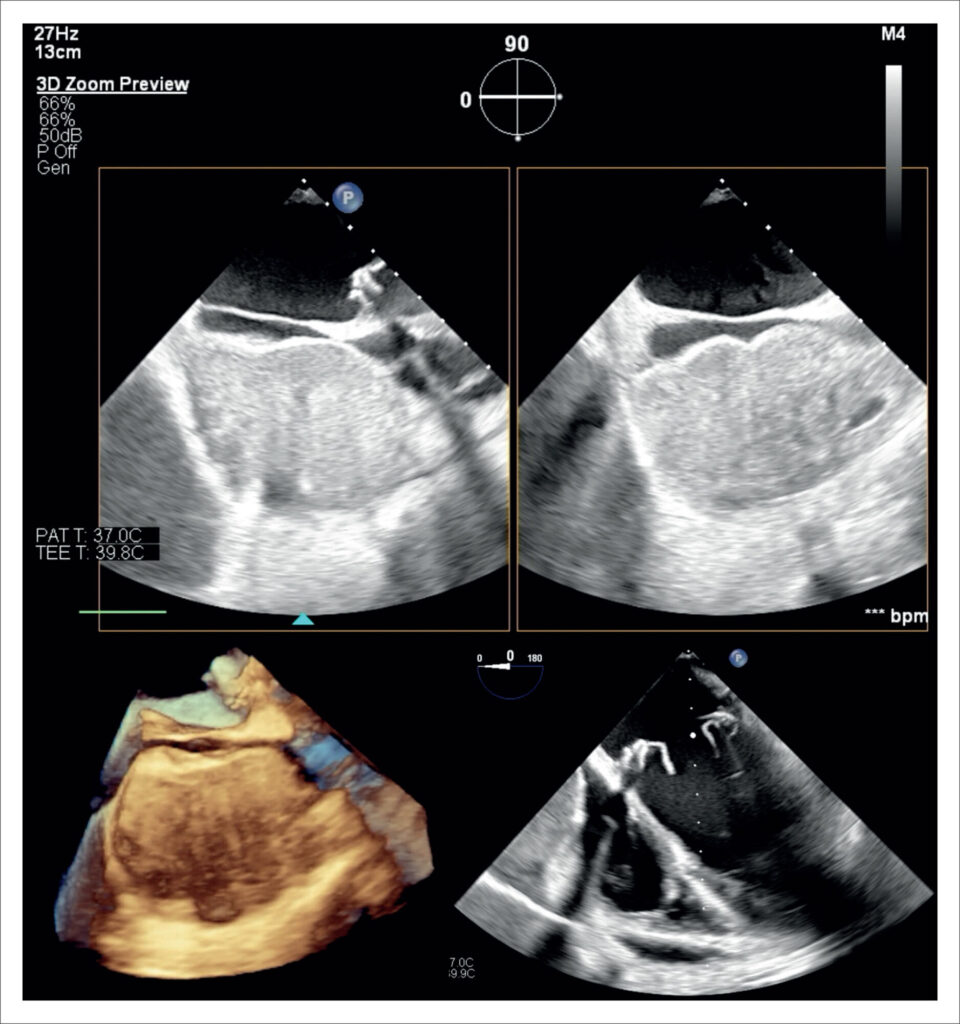

Pericardial Hematoma With Chest Pain and Tamponade in the Late Postoperative Period of Cardiac Surgery

This report describes an atypical presentation of pericardial hematoma, which manifested as severe chest pain on the 23rd postoperative day and rapidly progressed to hemodynamic instability. Echocardiography was instrumental in both diagnosing and managing the case, ultimately contributing to a favorable outcome.